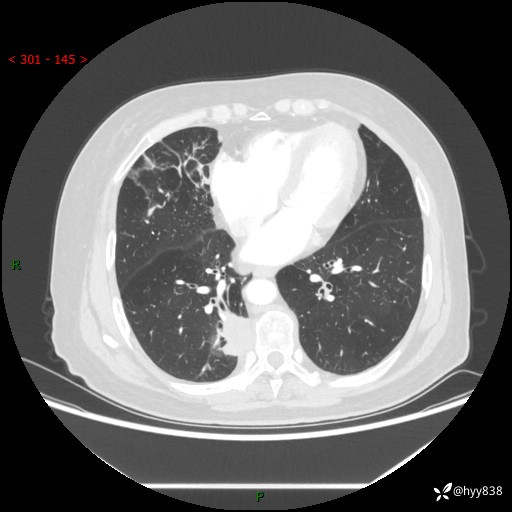

增强动脉期+静脉期

两期CT值:55Hu 53hu